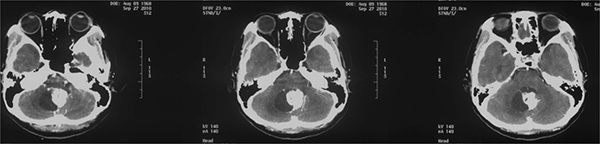

头颅增强MRI

1)T2像可见病变压迫延髓,有血管流空影。

2)增强像提示血供丰富。

3)矢状位提示肿瘤主体位于枕大孔背侧,瘤体巨大,最下缘至C1水平,最上缘至四脑室头端。